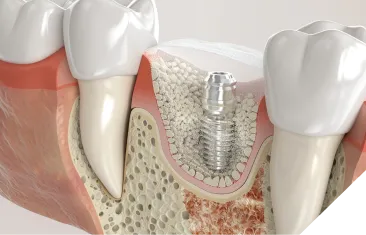

手術中の偶発的な事故

下顎には太い神経と血管が通る管(下顎管)が、上顎の奥には上顎洞という空洞があります。インプラントを埋め込む際にこれらを傷つけてしまうと、唇の麻痺や多量の出血といった重大な合併症を引き起こすリスクがあります。

当院では、歯科用CTによる3D精密診断を必ず行います。骨の厚みや高さはもちろん、神経や血管の位置をミリ単位で正確に把握します。さらに、そのデータをもとにコンピューター上で手術のシミュレーションを行い、安全な位置・角度・深さを決定し、治療計画を立案します。また、これに基づいて ガイドテンプレートを作製し、偶発的な事故のリスクを限りなくゼロに近づけます。

骨の厚みや高さの不足

歯を失ってから時間が経つと、顎の骨が痩せてしまい、インプラントを支えるための十分な厚みや高さがなくなることがあります。無理に埋入すると、安定せず脱落するリスクがあります。

当院の対策

骨が不足している方には、骨を増やす治療をご提案します。これにより、これまでインプラントは不可能と診断された方でも、安全に治療を受けられるようになります。当院ではこれらの処置にも対応可能です。